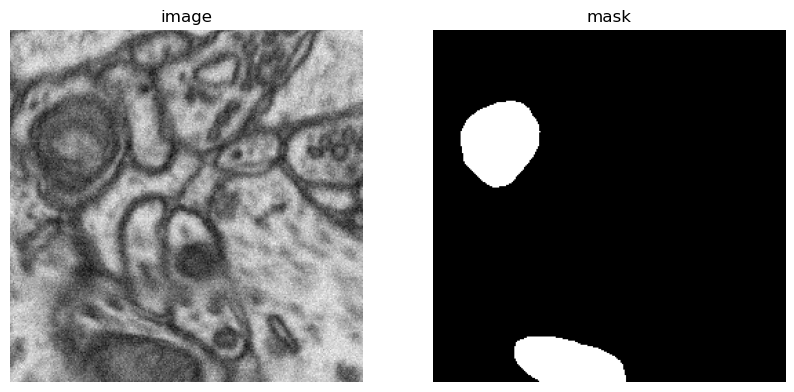

show_hf_dataset(dataset)

dataset index will be visualized: 300